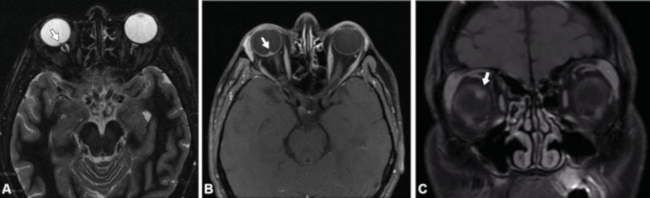

Por lo anterior, queremos compartir el caso de un paciente masculino de 38 años de edad con diagnóstico serológico de B. Henseleae, que consultó en nuestra institución por cuadrantopsia, metamorfopsia y edema de papila temporal en ojo derecho, y a quien se le realizó una RM de órbitas con contraste endovenoso, la cual mostró irregularidad en el polo posterior del globo ocular derecho asociado a señal hipointensa en secuencias ponderadas en T2/GRE y refuerzo patológico luego del contraste endovenoso (►Fig. 1).

La B. Henseleae invade el endotelio vascular, produciendo alteración en los mediadores trombogénicos, vasculitis obliterante y obstrucción de la arteria retiniana u oclusión venosa con afección de la cabeza del nervio óptico, lo que conlleva a inflamación masiva y alteración en la permeabilidad capilar.8 Eso puede manifestarse en RM como realce en un segmento corto del nervio óptico, con epicentro en su unión con el globo ocular (Schmalfuss y col.,9 mostraron una especificad del 98% de ese hallazgo). La neuroretinitis por B. Henselae suele tener un curso clínico favorable y autolimitado, presentando, la mayoría de los pacientes, recuperación completa de la agudeza visual en el transcurso de semanas a meses.